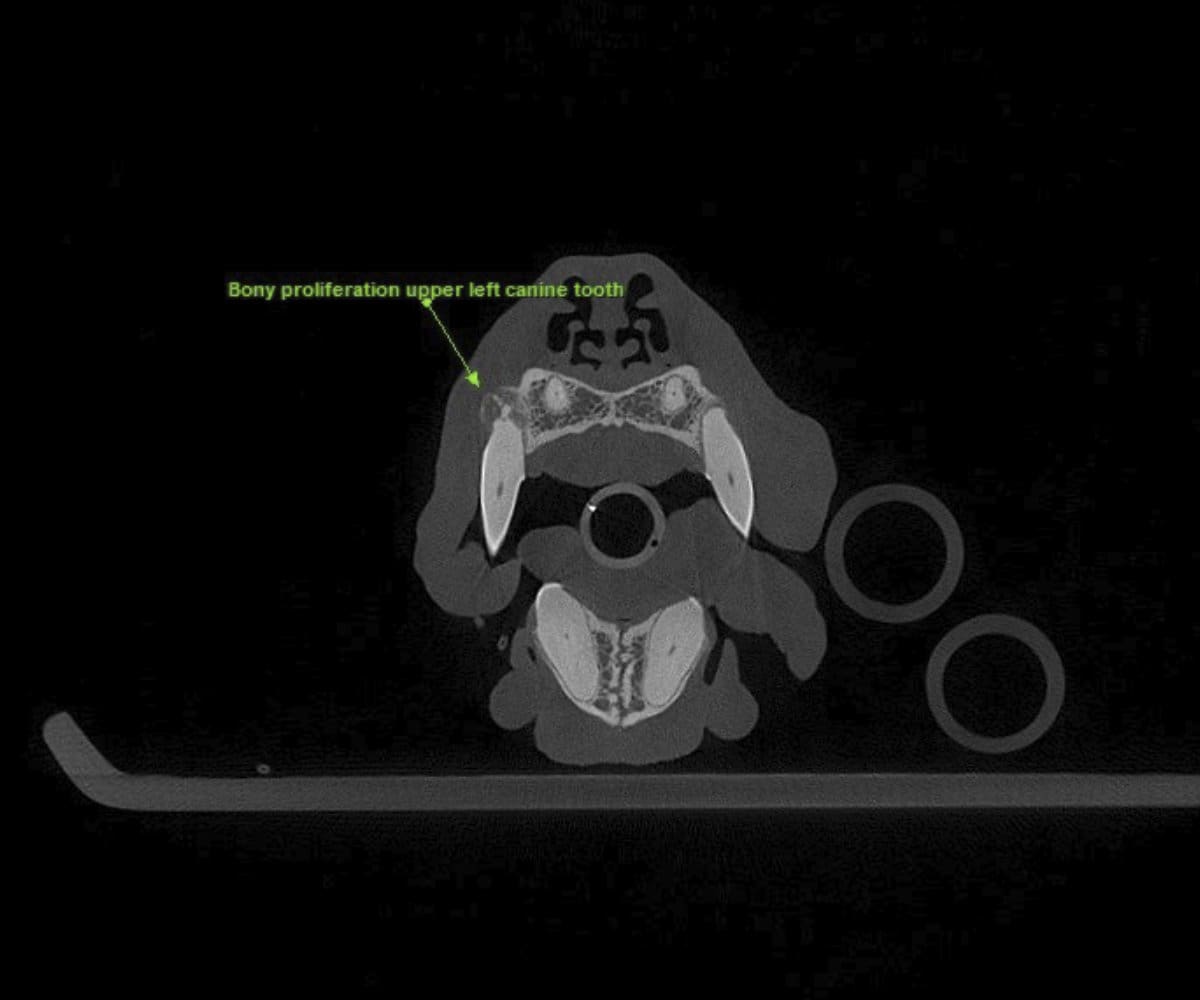

In addressing these limitations, CBCT emerges as a pivotal advancement. Conducting a CBCT scan on our patients is characterized by minimal time and effort, effectively reducing anesthesia duration. Moreover, this technology facilitates the generation of a comprehensive 3D reconstruction of the teeth and skull, surpassing the constraints of traditional radiographs. This innovative approach empowers our veterinary professionals to identify oral pathologies that may have been missed on traditional radiographs.

Cone beam CT technology provides veterinarians with 3-dimensional images in far greater detail than dental radiographs. CBCT scans significantly decrease the amount of time a patient spends under anesthesia compared to the time it takes to complete dental radiographs.

Our CBCT VetCAT unit is easily rolled up to our treatment table and takes only 40 seconds to complete a scan. It has proven to be invaluable in the diagnosis and treatment planning for pets with periodontal, endodontic and cancerous disease conditions. It is also indispensable in the evaluating our trauma cases with jaw fractures.